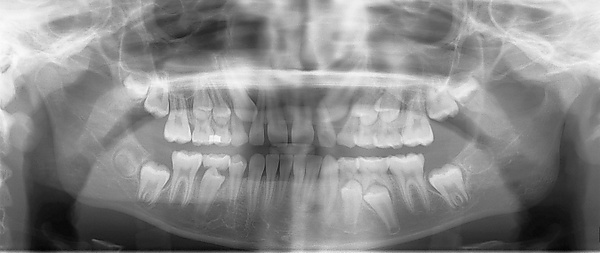

Ортопантомография (от греч.: orthos — прямой, правильный, pan — всё, tomos — ломоть, отрезанный кусок и grapho — писать, рисовать) — особый вид рентгеновской съёмки костей лицевого скелета, при котором они «развёртываются» в одну плоскость[1]. Другими словами рентгенологическое исследование в стоматологии, челюстно-лицевой хирургии, косметологии, позволяющее получать развёрнутое изображение всех зубов с челюстями, прилежащими отделами лицевого скелета. Является первичным рентгенологическим исследованием[2].

Галерея